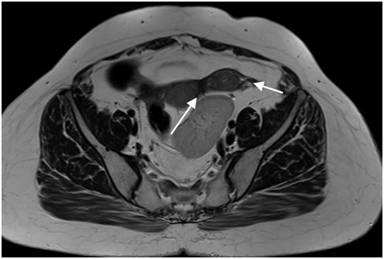

Figure 4. Axial T2 weighted MR image showing two horns of bicornuate uterus (arrows) and kidney in pelvis. |

The uterus, fallopian tubes and the upper part of the vagina develop from the paramesonephric ducts which develop as an outpouching from the urogenital ridge along the posterior abdominal wall. The caudal part of these ducts fuse to form single uterine cavity while the cranial parts remain separate to form the paired fallopian tubes. Failure/anomalous development/ lack of fusion of these ducts are not uncommon giving rise to myriad of mullerian anomalies and the imaging technique of choice for evaluation is MRI. These have been classified by the American fertility society into various classes of which bicornuate uterus represents class IV. On imaging bicornuate uterus is characterized by deep fundal cleft >1 cm, increased intercornual distance of >4 cm and intercornual angle of >105 degrees [11-12].